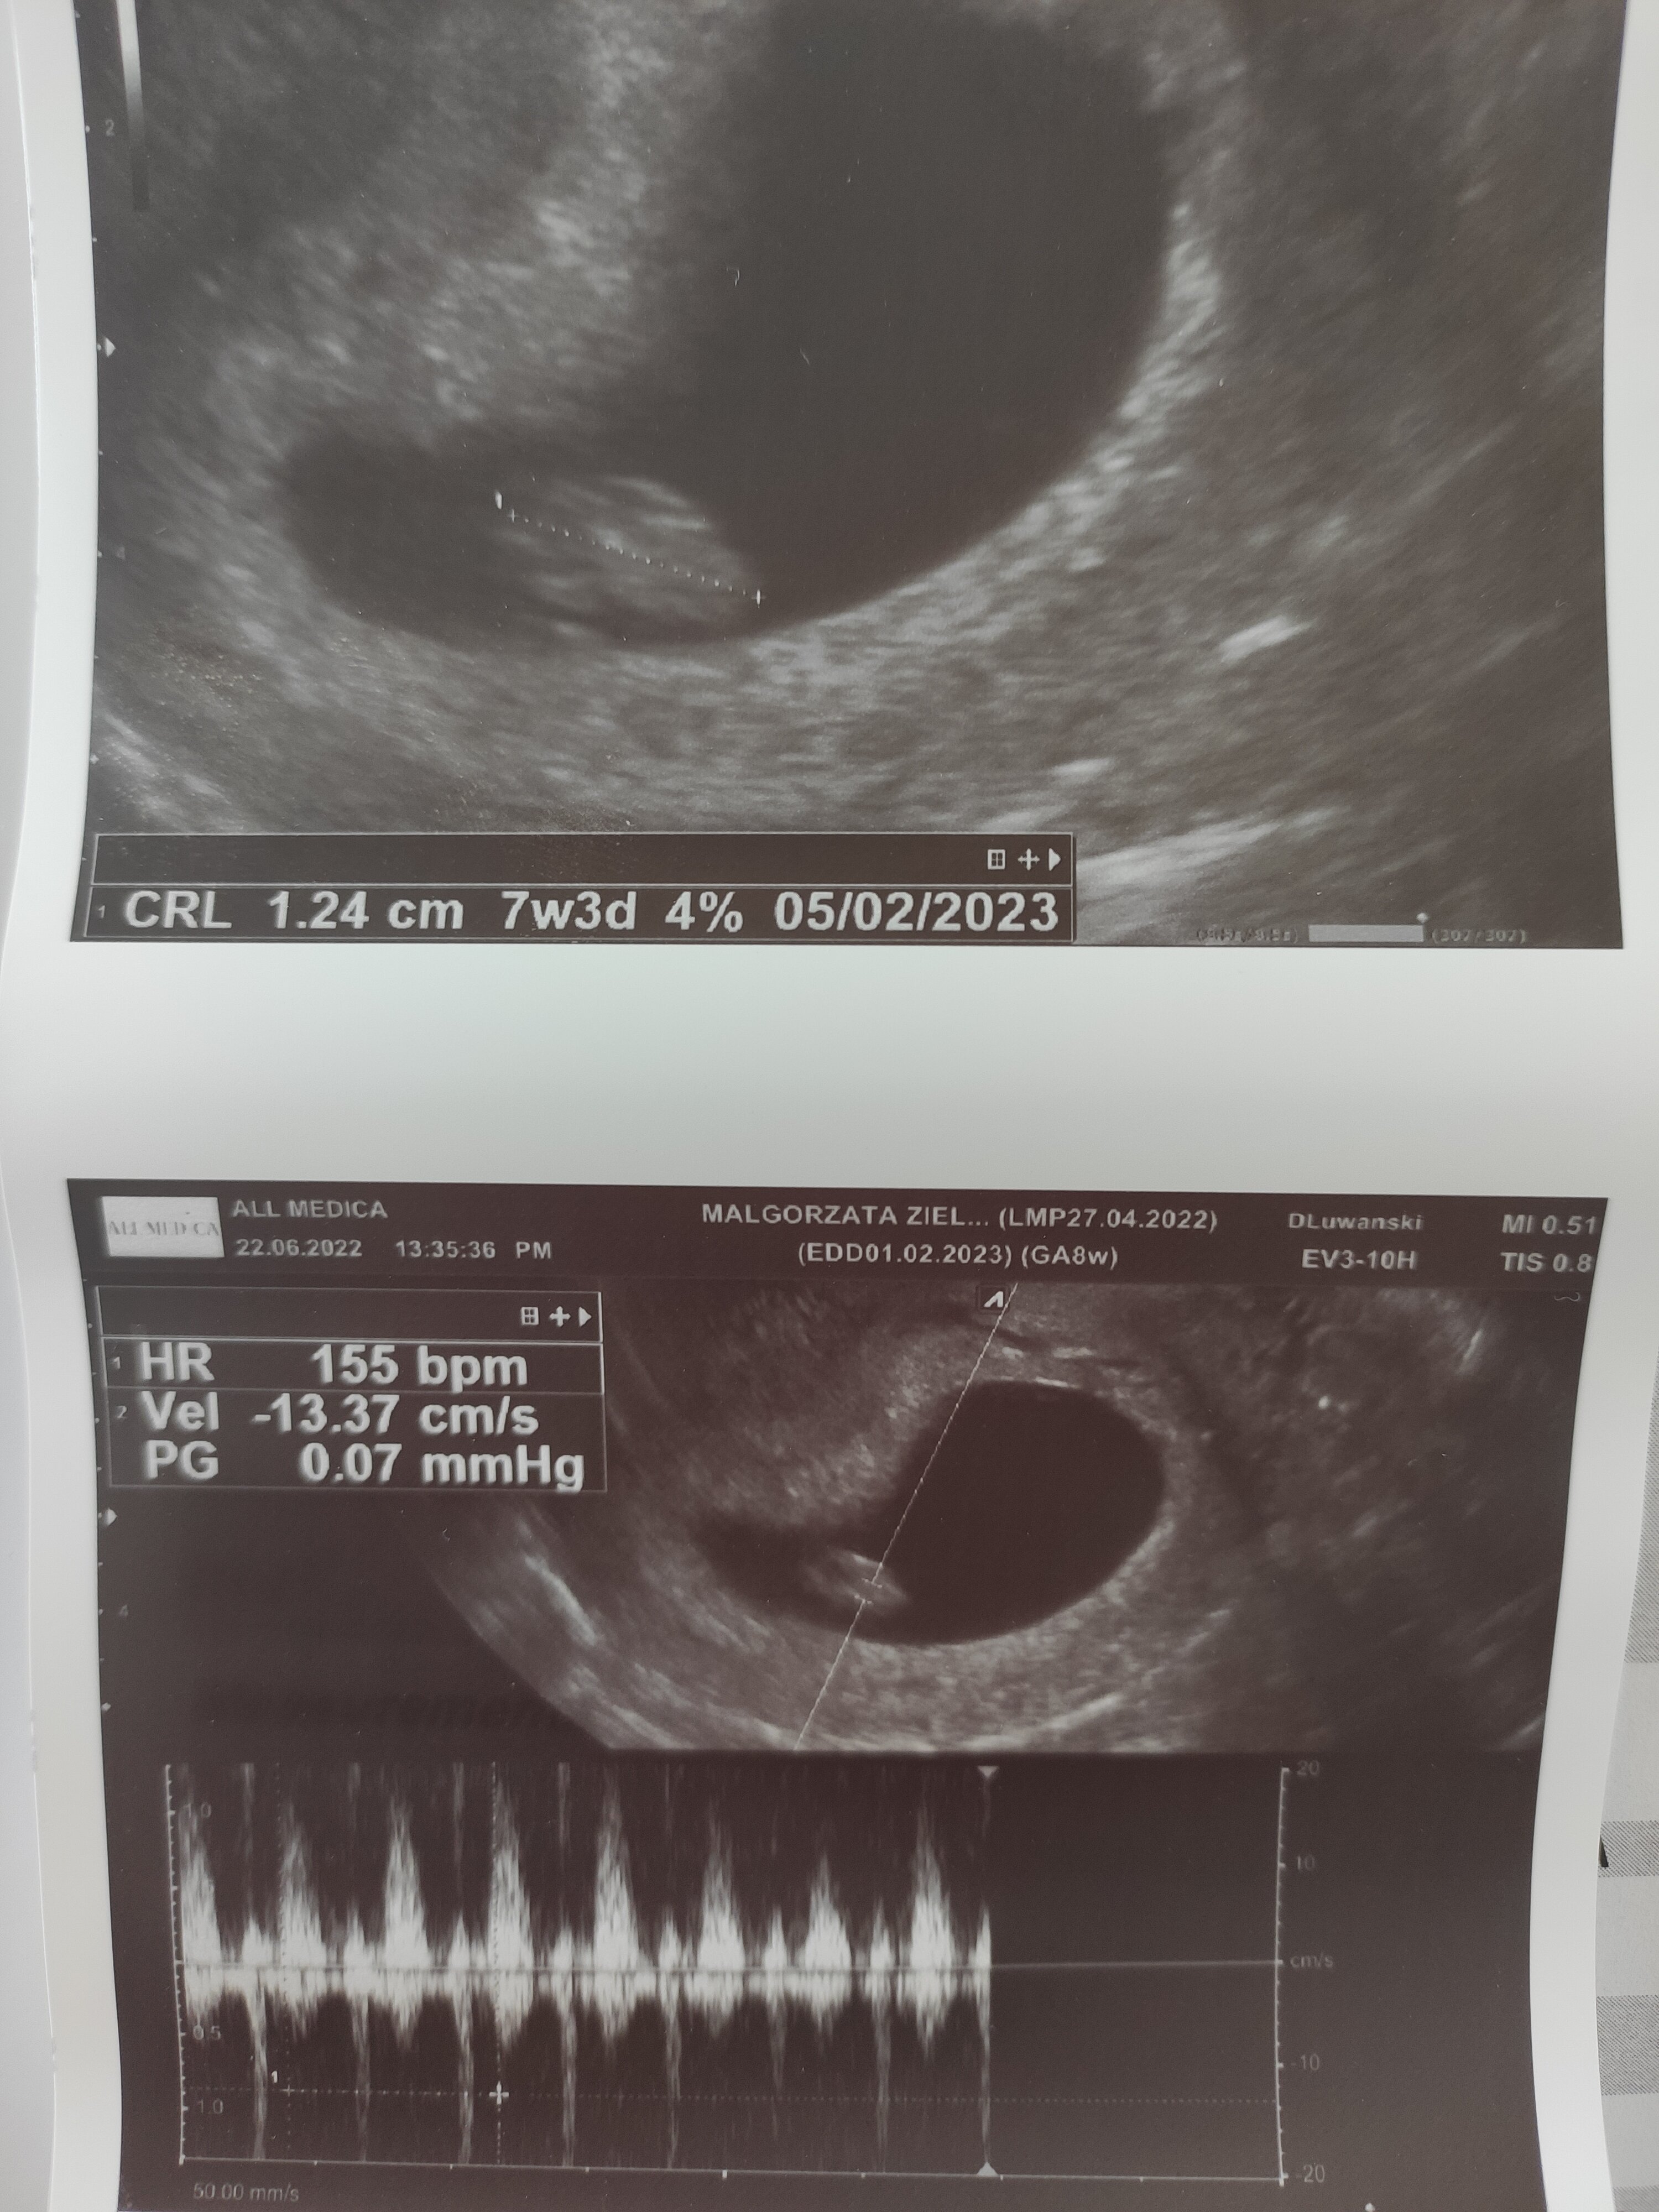

Właśnie jestem po USG, wszystko dobrze, jest zarodek i serduszko ♥️ Ciąża jest młodsza o 4 dni i trzeba było troszkę dłużej poczekać 😊